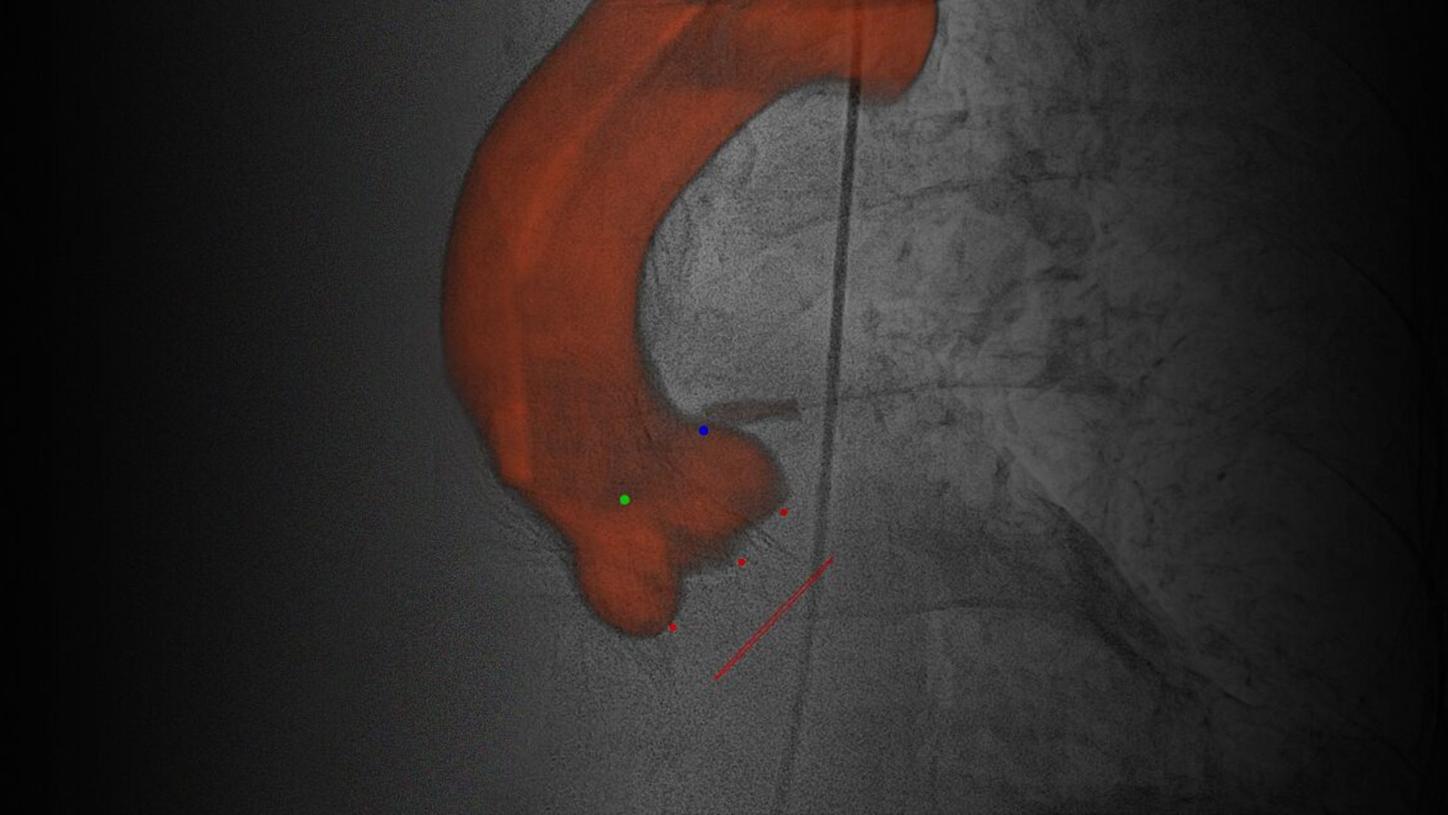

Simple and fast 3D imaging, everywhere

Generate 3D acquisitions with excellent spatial and soft tissue resolution whatever your clinical case is. With up to 95°/s rotation speed, ARTIS icono systems can acquire syngo DynaCT images in just 2.5 seconds with fewer motion artifacts and less use of contrast media.3 Simple and fast 3D imaging from head to toe with 200° rotation range gives you confidence in procedure planning.